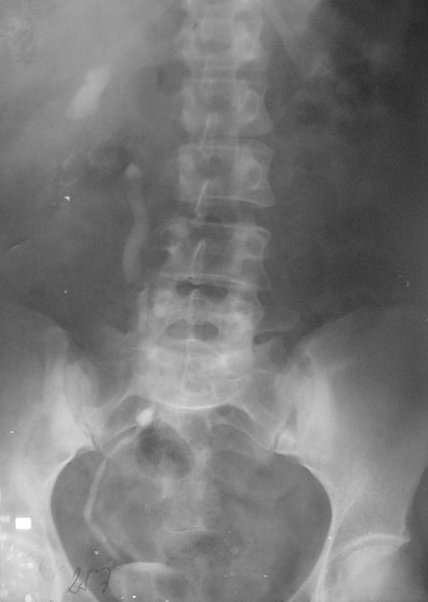

Aparatul renal

Anomalii reno-ureterale

Litiaza renală, ureterală, vezicală

Hidronefroza

Tuberculoza reno-ureterală

Tumorile renale